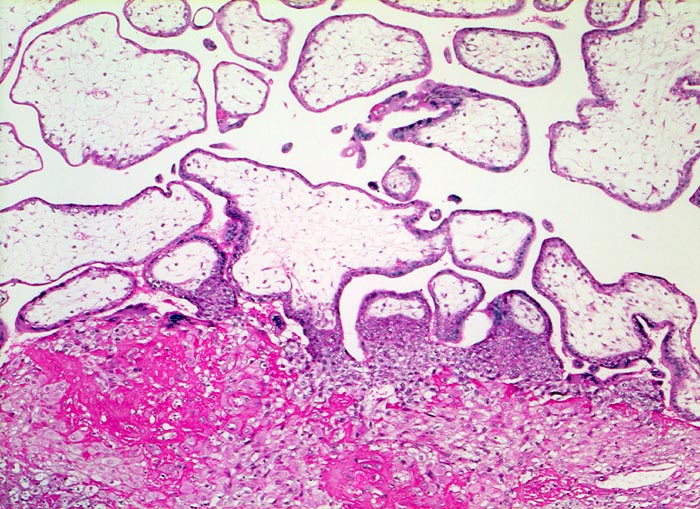

Gravidität: Haftzotten

Unten im Bild die hellen zytoplasmareichen Zellen der Dezidua durchmischt mit einer Schicht von hypereosinophilem Fibrinoid. Ein Teil der Zotten, die Haftzotten, sind über proliferiertes Trophoblastepithel mit der Dezidua verankert. Kernknospe.

11. Schwangerschaftswoche. Normale Schwangerschaft

Kernknospen sind knospenförmige Ansammlungen von Kernen an der Zottenoberfläche. Sie treten in jeder normalen Plazenta auf. Sie sind gehäuft anzutreffen im Randbezirk von Infarkten und bei vermindertem Sauerstoffangebot (sogenanntes Tenney Parker Zeichen)